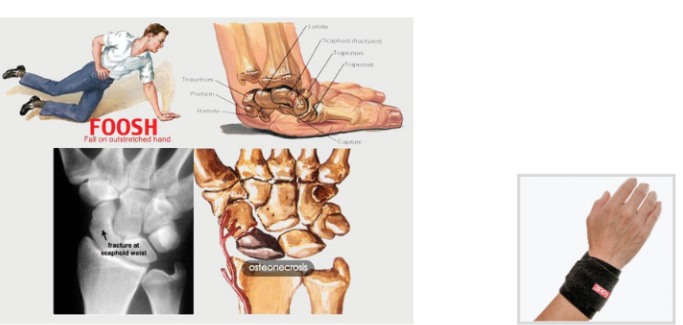

1. Cái Bẫy “FOOSH”: Phản Xạ “Chống Tay” Chết Người

Khi bị ngã (đặc biệt là ngã ngửa khi lùi cứu lob hoặc ngã tới khi rướn cứu bóng thấp), phản xạ tự nhiên của 99% mọi người là duỗi thẳng cánh tay ra để chống xuống đất.

Trong y học, đây là nguyên nhân gây ra chấn thương FOOSH (Fall On OutStretched Hand – Ngã Chống Lên Bàn Tay Duỗi Thẳng).

- Tại sao nguy hiểm? Toàn bộ trọng lượng cơ thể và lực tác động của cú ngã bị dồn vào một điểm duy nhất: cổ tay mỏng manh của bạn. Lực này sau đó truyền lên, gây gãy xương khuỷu tay, trật khớp vai hoặc gãy xương đòn.

- Hậu quả: Gãy cổ tay là một trong những chấn thương phổ biến nhất và gây phiền toái nhất trong Pickleball.

=> Quy Tắc Vàng #1: Mục tiêu của việc ngã an toàn là KHÔNG BAO GIỜ tiếp đất bằng một cánh tay duỗi thẳng.